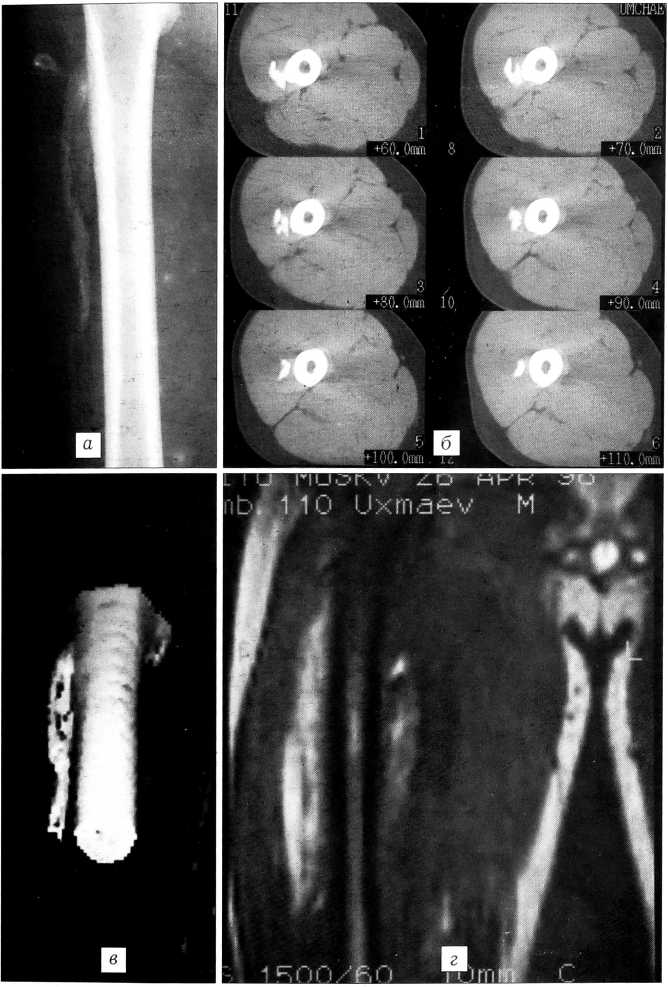

На рентгенограммах правого бедра определяется дополнительное пароссальное лентовидное образование костной плотности с неровным нечетким контуром, располагающееся по ходу мышечных волокон. Поверхность бедренной кости четкая, ровная, периостальных наслоений нет (рис. 1, а) Компьютерная томография: пароссальное образование локализуется в толще m. vastus lateralis, имеет костную плотность и на протяжении 2 см связано с бедренной костью (рис. 1, б, в). Магнитно-резонансная томография в режиме Т2 взвешенности: пароссальное образование имеет гиперинтенсивный, гетерогенный сигнал (рис. 1, г). Выявленные изменения расценены как гетеротопический оссификат.

Рис. 1. Больной У. Гетеротопический оссификат правого бедра. а — рентгенограмма правого бедра: пароссальный оссификат лентовидной формы с четкими контурами по ходу m. vastus lateralis; б — компьютерная томограмма: пароссальный оссификат связан с бедренной костью и располагается в толще мышцы по ходу ее волокон; в — компьютерная томограмма: пароссальный оссификат в режиме 3D реконструкции; г — магнитно-резонансная томограмма: гиперинтенсивный гетерогенный сигнал в режиме Т2 взвешенности.

Через 4 мес после травмы произведена операция. Оссификат полностью располагался в толще наружной порции четырехглавой мышцы, проксимальный отдел его был спаян костным мостиком 2x2 см с наружной поверхностью бедренной кости. Оссификат отсечен долотом. Костная рана покрыта парафином. Активное дренирование ложа оссификата в течение 1 сут. Четырехкратное инфильтрирование краев раны раствором гидрокортизона (50 мг в 10 мл новокаина) с интервалом 1-3 сут. Иммобилизация. Восстановительное лечение через 18 дней. Лечение ксидифоном 3 мес.